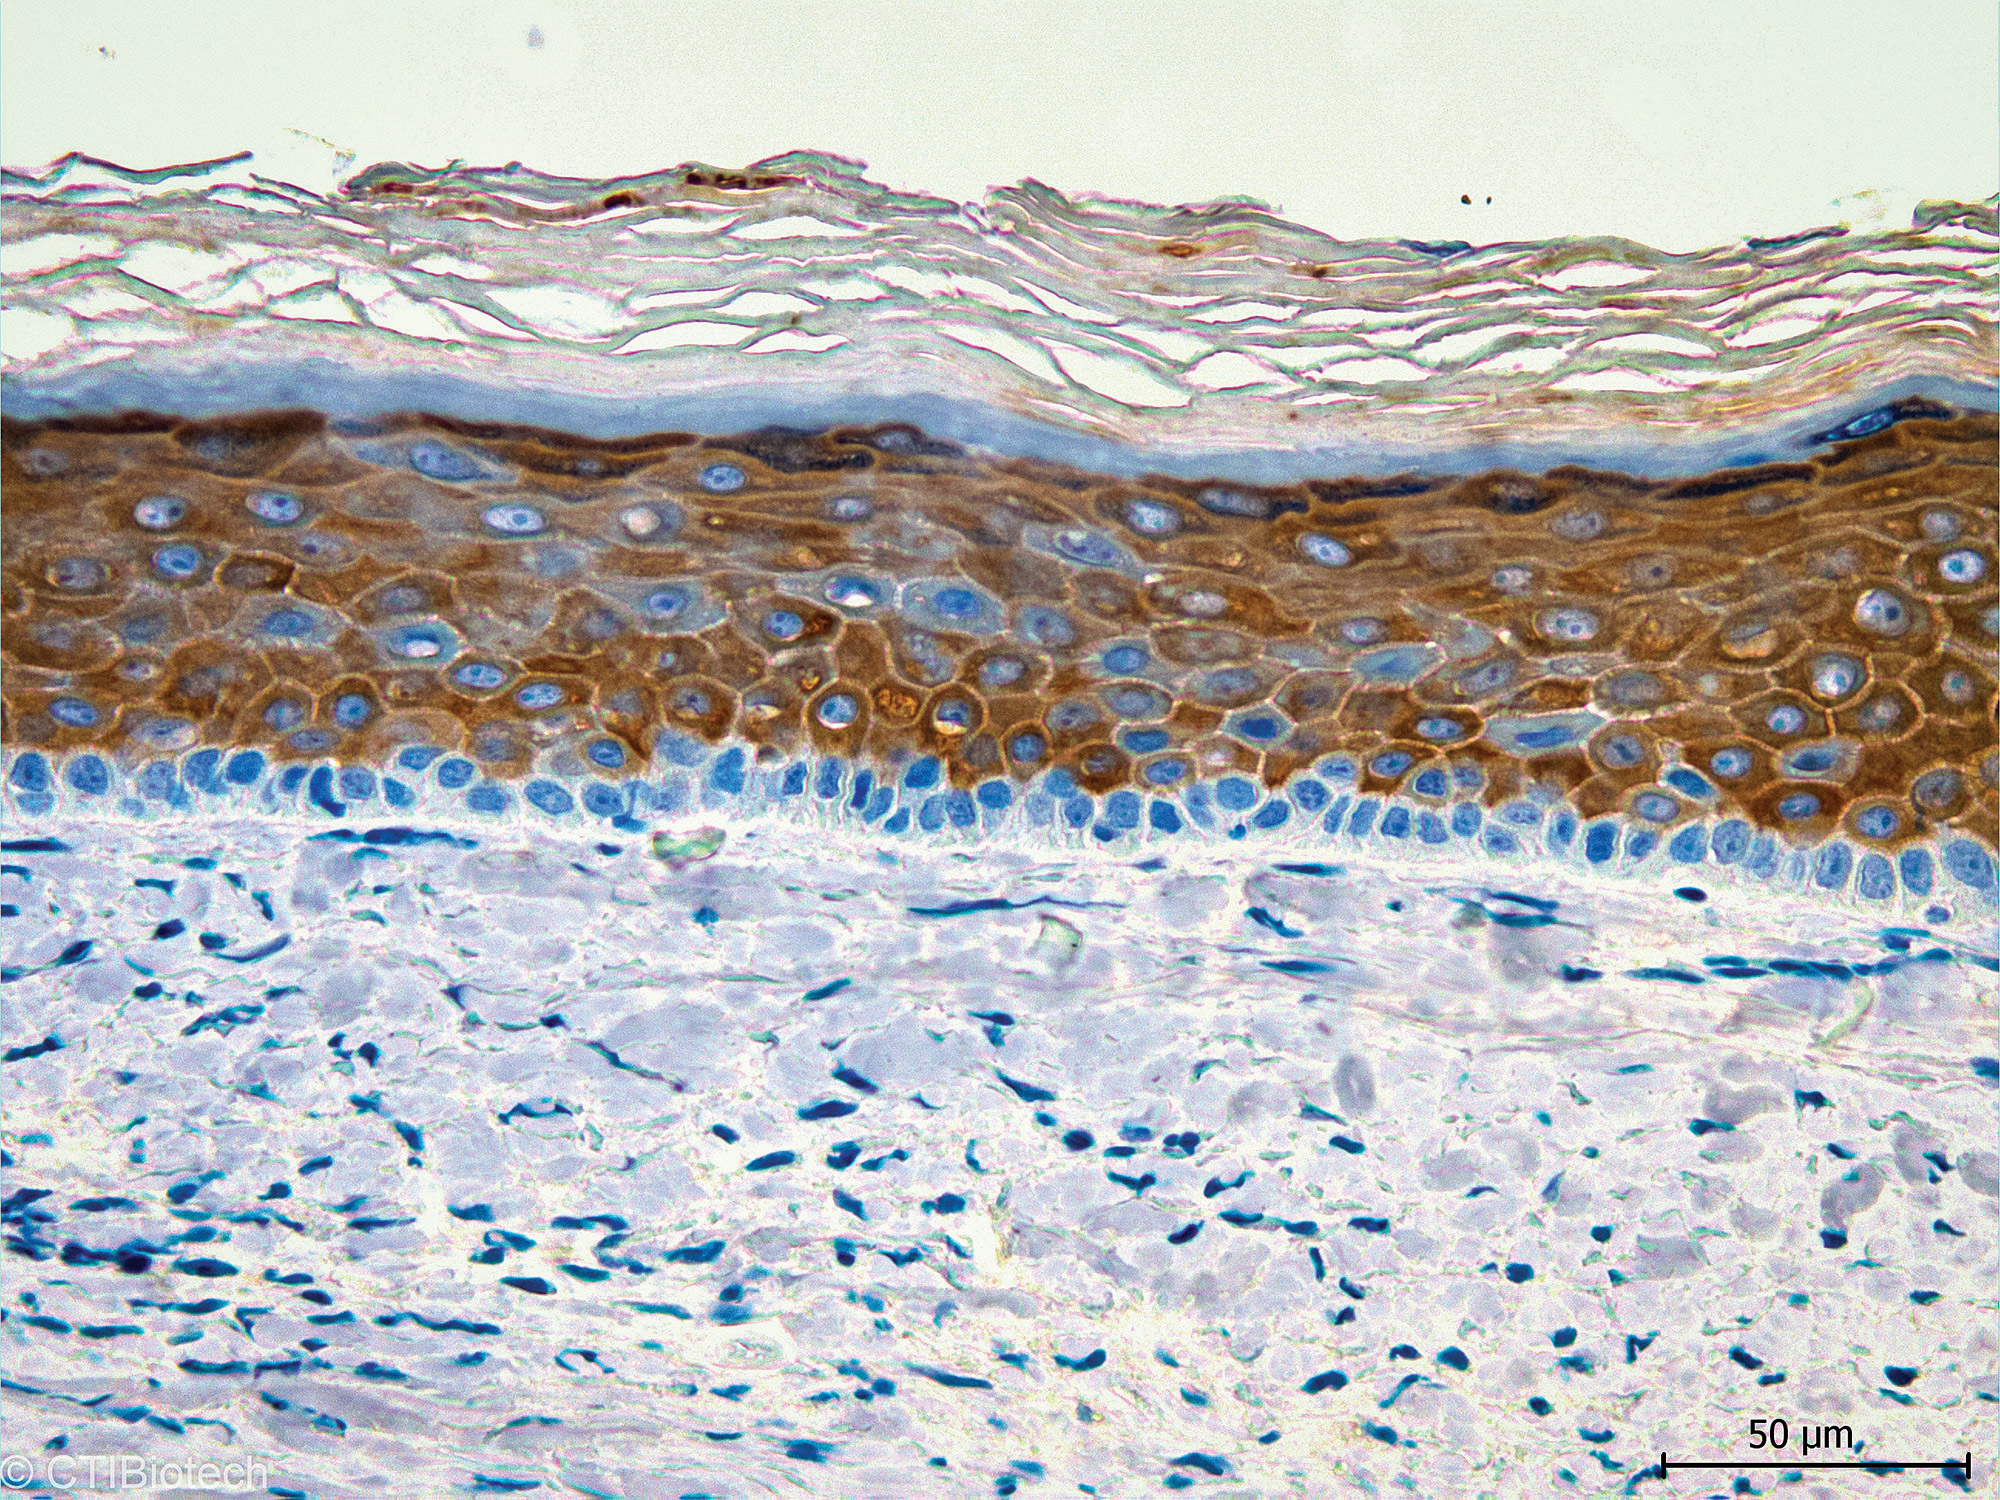

BASF y CTIBiotech desarrollan la primera piel reconstruida humana bioimpresa en 3D que incluye macrófagos inmunes